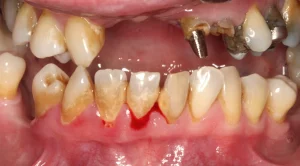

This gentleman felt that he had let his mouth go and was ready to get them sorted out. Even though he had most of his teeth, they were heavily decayed, abscessed, split and loose. Regrettably, his upper and lower teeth were past saving and were removed.

We placed eight upper jaw and six lower jaw implants. These were then joined with a bar.